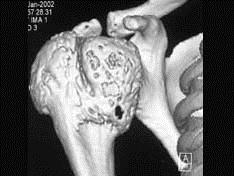

问题 男,29岁,右肩肿物4年,质地硬,压痛不明显,请结合图像,选择最佳答案 ( )

选项 A、巨细胞瘤 B、软骨肉瘤 C、骨转移瘤 D、成软骨细胞瘤 E、结核

答案 D